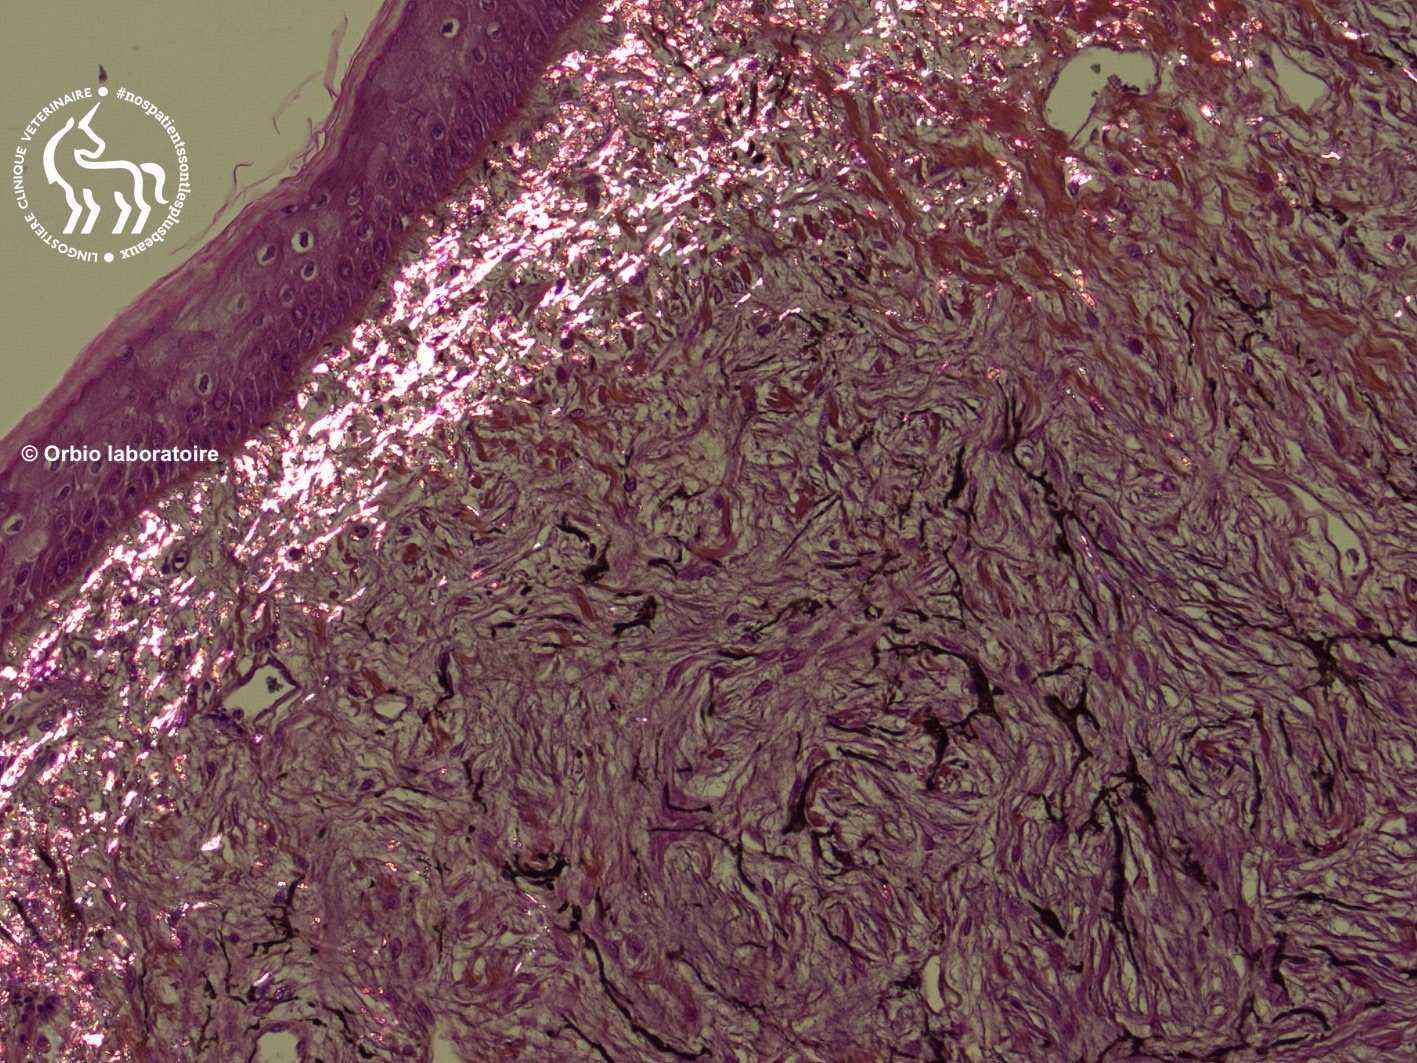

Analyse Histopathologique

Le diagnostic de certitude repose exclusivement sur l’examen microscopique des tissus prélevés.